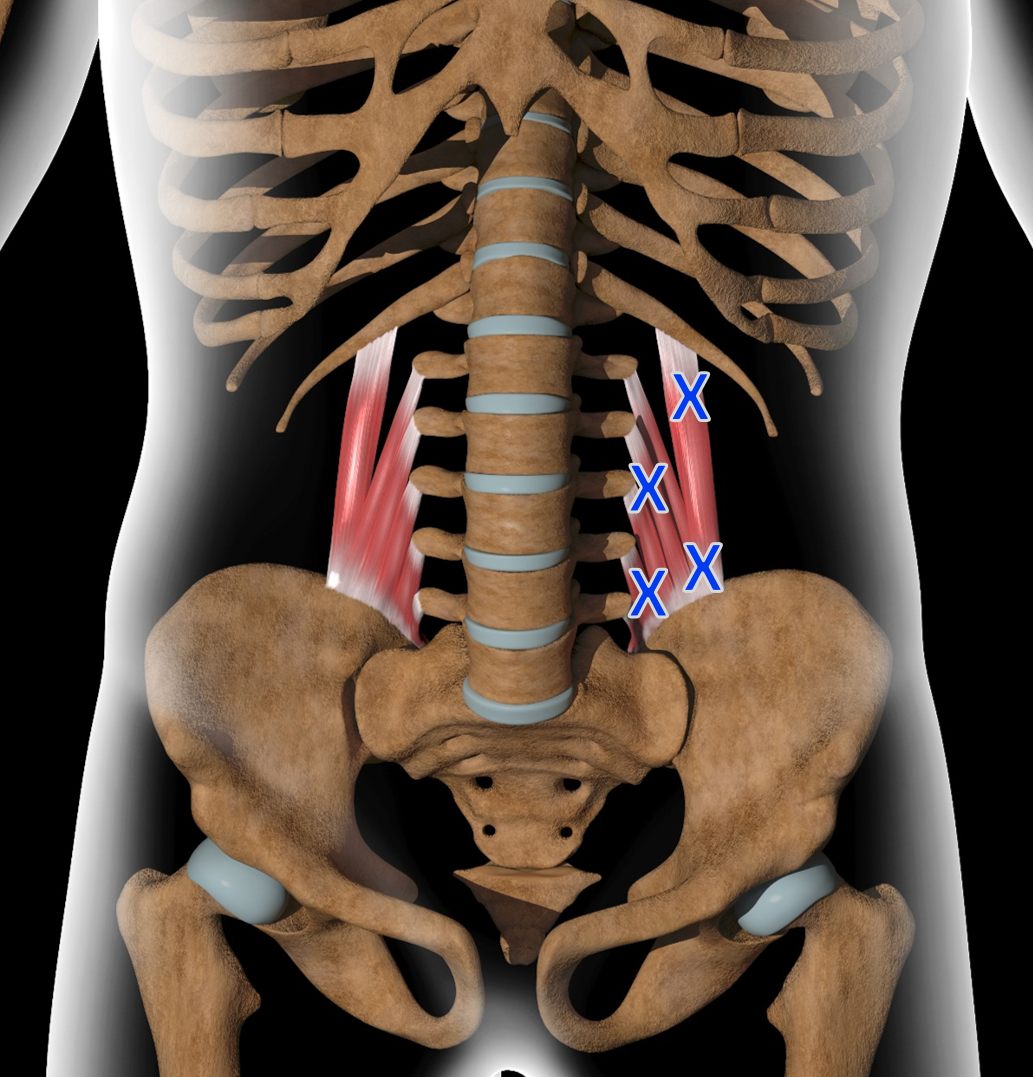

Θαμμένος βαθιά κάτω από τους παχιούς επιφανειακούς μύες της πλάτης σας, βρίσκεται ένας ορθογώνιος μυς σε κάθε πλευρά της σπονδυλικής σας στήλης που ονομάζεται Τετράγωνος Οσφυικός μυς (Quadratus Lumborum). Συνδέει το χαμηλότερο πλευρό σας (το 12ο πλευρό), τις εγκάρσιες διαδικασίες των οσφυϊκών σας σπονδύλων και την κορυφή της λεκάνης σας (το λαγόνιο άκρο).

Όταν κάθεστε άνισα, κουβαλάτε μια βαριά τσάντα στον έναν ώμο ή κοιμάστε σε μια στριμμένη θέση, η μία πλευρά του Τετράγωνου Οσφυϊκού σας, υπερλειτουργεί. Αναπτύσσει πυκνά σημεία ενεργοποίησης (οι λαμπεροί λευκοί κόμποι στην εικόνα) και γίνεται απίστευτα ευερέθιστος.